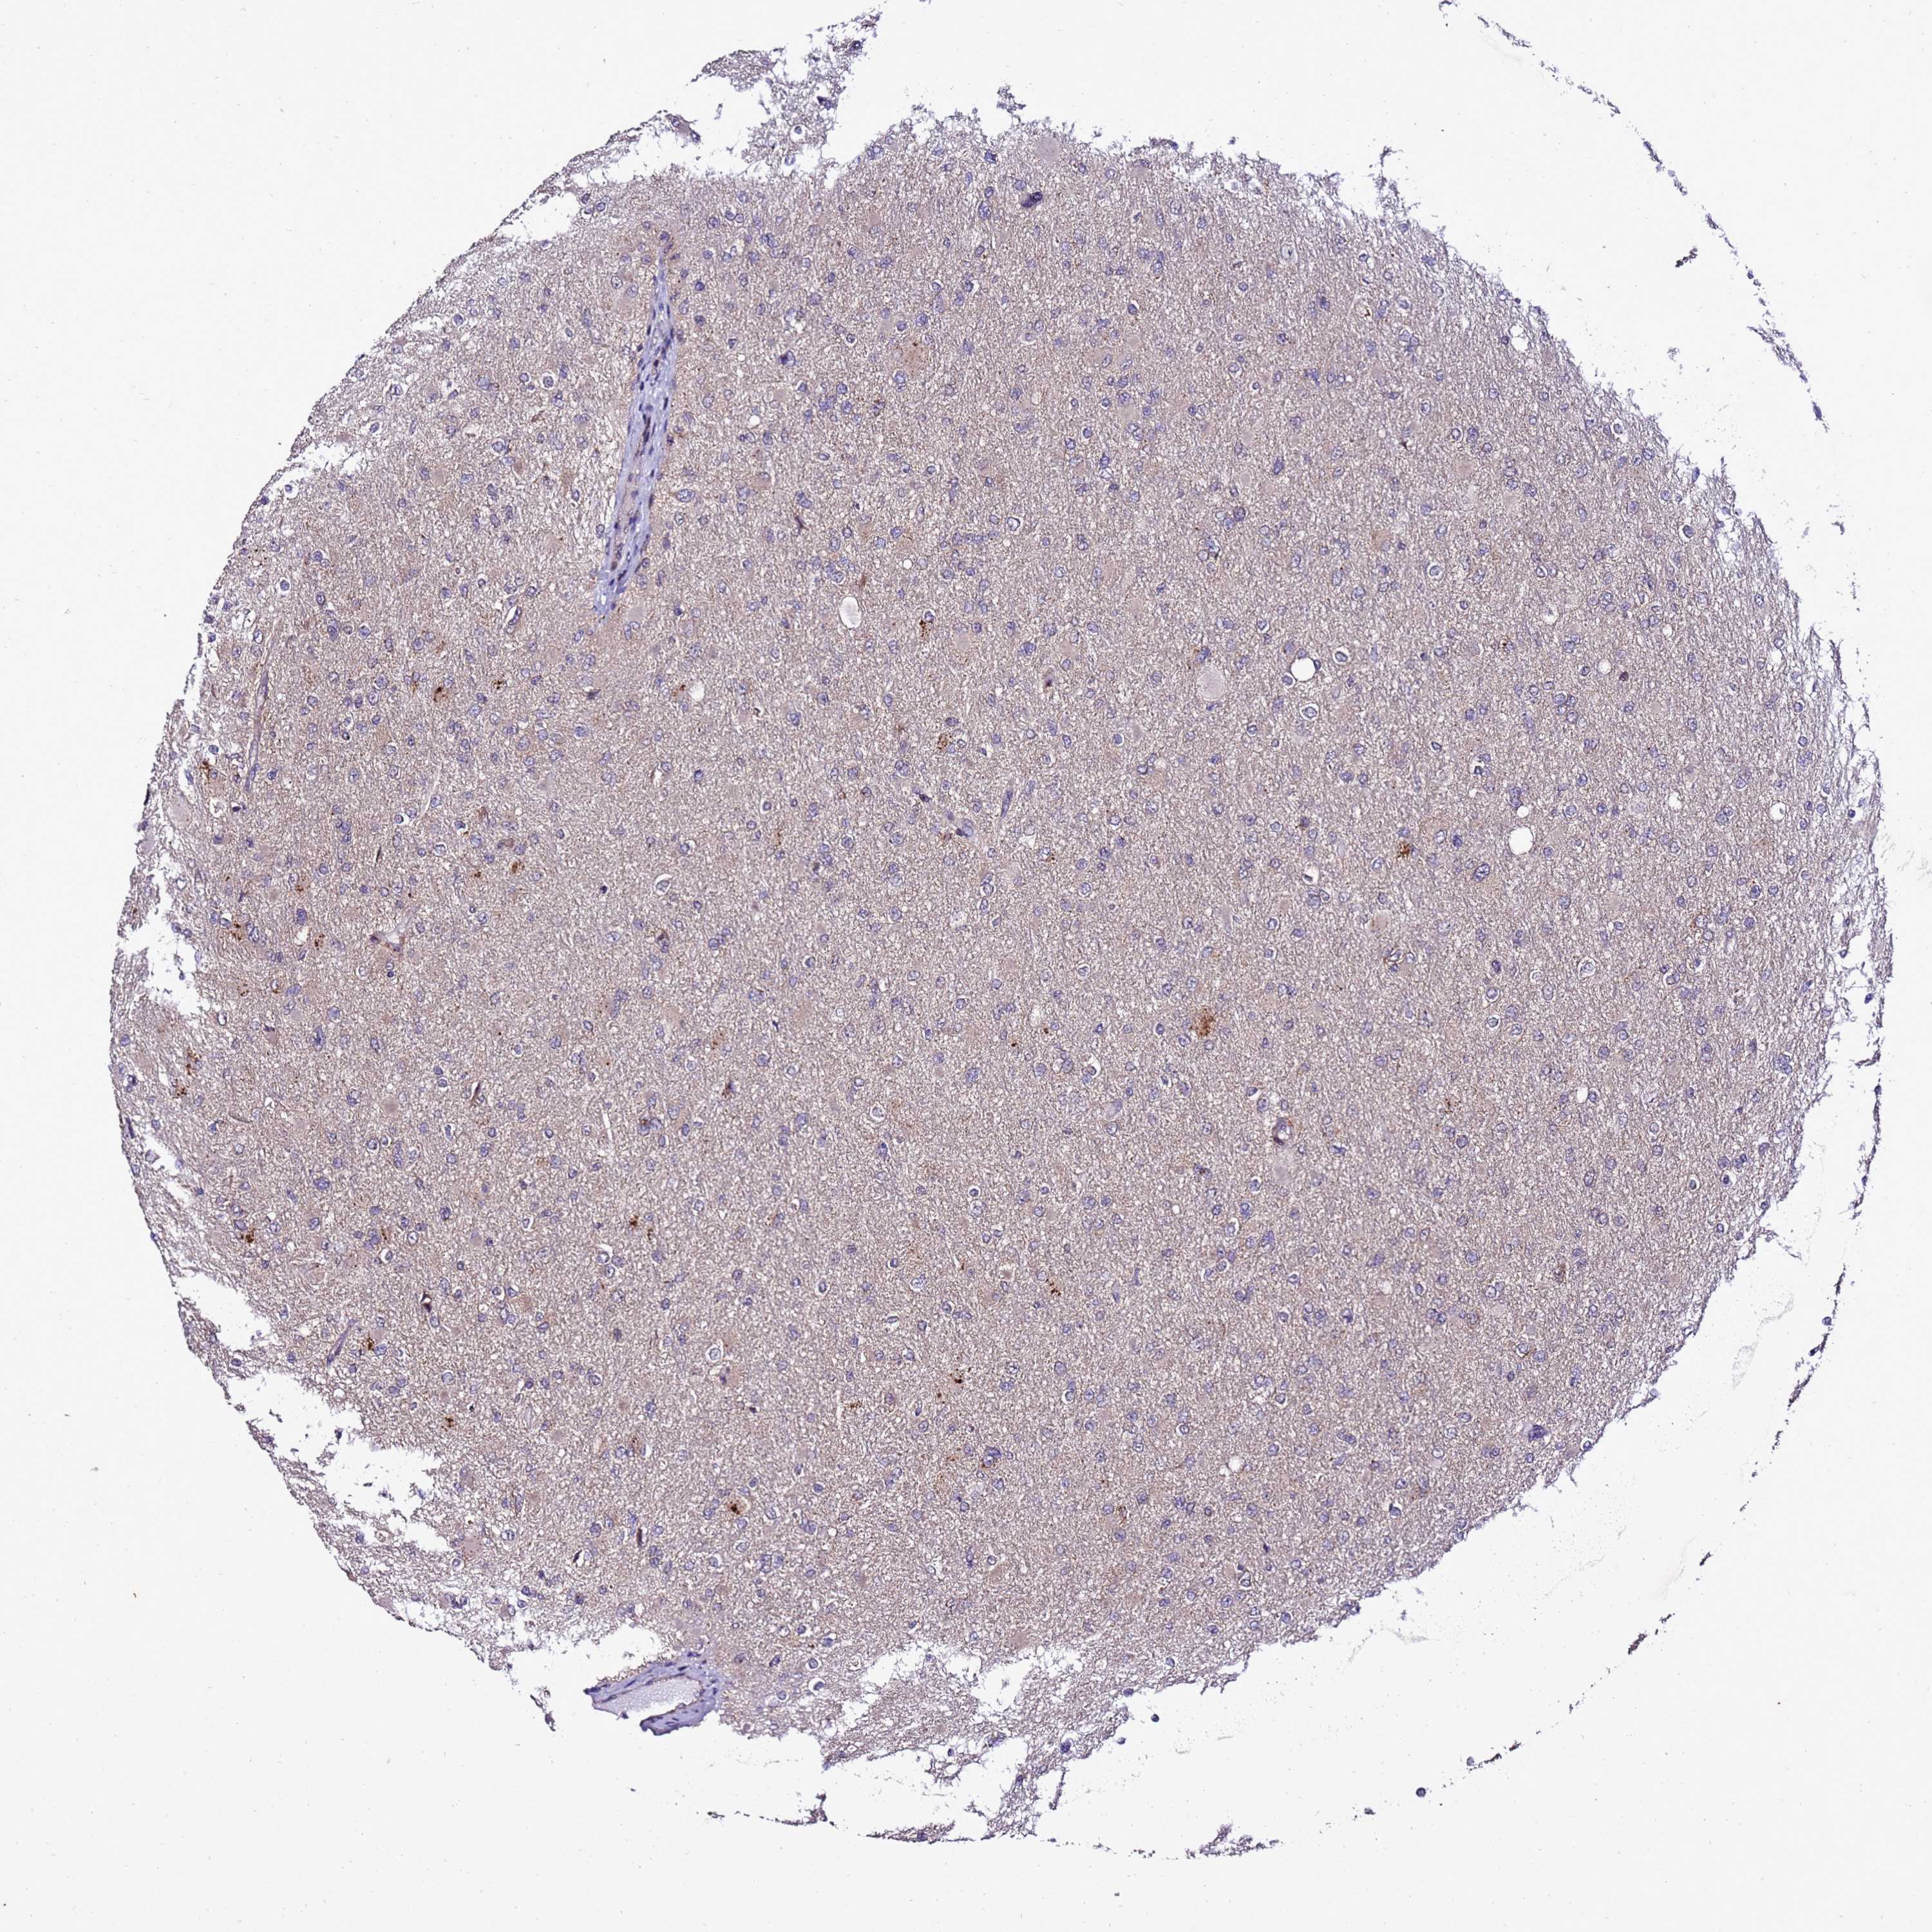

GLIOMA - Protein expressioni

A mouse-over function shows sample information and annotation data. Click on an image to view it in a full screen mode. Samples can be filtered based on level of antibody staining by selecting one or several of the following categories: high, medium, low and not detected. The assay and annotation is described here.

Note that samples used for immunohistochemistry by the Human Protein Atlas do not correspond to samples in the TCGA dataset.

Antibody stainingi

Antibody staining in the annotated cell types in the current human tissue is reported as not detected, low, medium, or high, based on conventional immunohistochemistry profiling in selected tissues. This score is based on the combination of the staining intensity and fraction of stained cells.

Each image is clickable and will lead to virtual microscopy that enables deeper exploration of all samples and also displays staining intensity scores, fraction scores and subcellular localization as well as patient and tissue information for each sample.

Antibody HPA044373

Staining

High

Medium

Low

Not detected

Intensity

Strong

Moderate

Weak

Negative

Quantity

>75%

75%-25%

<25%

None

Location

Nuclear

Cytoplasmic/membranous

Cytoplasmic/membranous,nuclear

Glioma, malignant, High grade

Glioma, malignant, Low grade

Glioblastoma, NOS